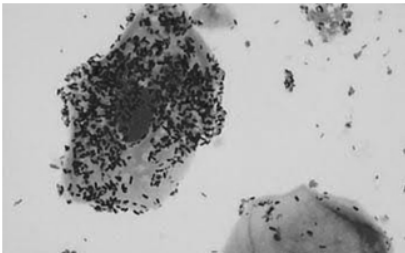

Uma gestante com dezesseis semanas e quatro dias compareceu ao pronto-atendimento com queixa de “corrimento vaginal” há quatro dias. O teste das aminas foi positivo e o exame especular é ilustrado na figura 1. Após a realização de coloração Gram, o resultado pode ser observado na figura 2.

Figura 2